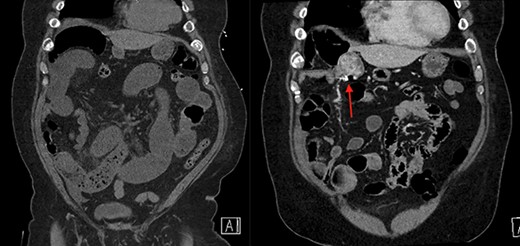

On the left is the initial CT scan non-contrast demonstrating no obvious mass. On the left is the CTA, a week later, showing a mass and pill cam in the right upper quadrant.

The patient is a 69-year-old male with a past medical history of hypertension, chronic kidney disease, chronic obstructive pulmonary disease, right renal cancer status post-laparoscopic nephrectomy in 2016 (pathology showed renal cell carcinoma with invasion into the adrenal gland, Fuhrman nuclear grade 3–4, pT4 pN0, Stage IV) who presented to the emergency room (ER) with abdominal pain. The patient recently underwent an esophagogastroduodenoscopy and a colonoscopy the week prior as a workup for anemia, which were unremarkable. Since then, he started having intermittent abdominal pain and bloating. The CT abdomen and pelvis without contrast in the ER showed multiple dilated small bowel loops with a transition point in the right lower quadrant (Figs 1 and 2). Due to his history of previous abdominal surgery, this was diagnosed as a small bowel obstruction secondary to adhesions. He was initially managed with a nasogastric tube and gastrografin study. On hospital Day 1, he had minimal output from his nasogastric tube and started to have bowel movements; therefore, his nasogastric tube was removed and he was started on a liquid diet. His diet was advanced, and on hospital Day 2, the patient was discharged.

The next week, unbeknownst to his Gastroenterologist about his recent small bowel obstruction admission, he then proceeded with a capsule endoscopy study to assess for other causes of his anemia. He tolerated the pre-operative bowel preparation without issues. After swallowing the capsule, he subsequently had bloody bowel movements. He then went to the ER and found to have a hemoglobin of 7.1, which was decreased from his prior week’s hospitalization, 8.4. A CT angiography (CTA) abdomen and pelvis was then performed that showed a 4 × 6 × 4.1 cm mass in the right upper quadrant with the capsule endoscopy at the level of the mass (Figs 1 and 2). The images from the capsule were unremarkable. On review of his imaging with radiology, it appeared that this mass was not apparent without IV contrast on his previous CT scan a week prior. In addition, a prior CT abdomen pelvis with IV contrast 10 months ago was negative for a small bowel mass. A repeat abdominal and pelvis CT with oral and IV contrast was done for confirmation. This re-demonstrated the 6 cm mass with the capsule stuck proximal to it; therefore, we performed a diagnostic laparoscopy.